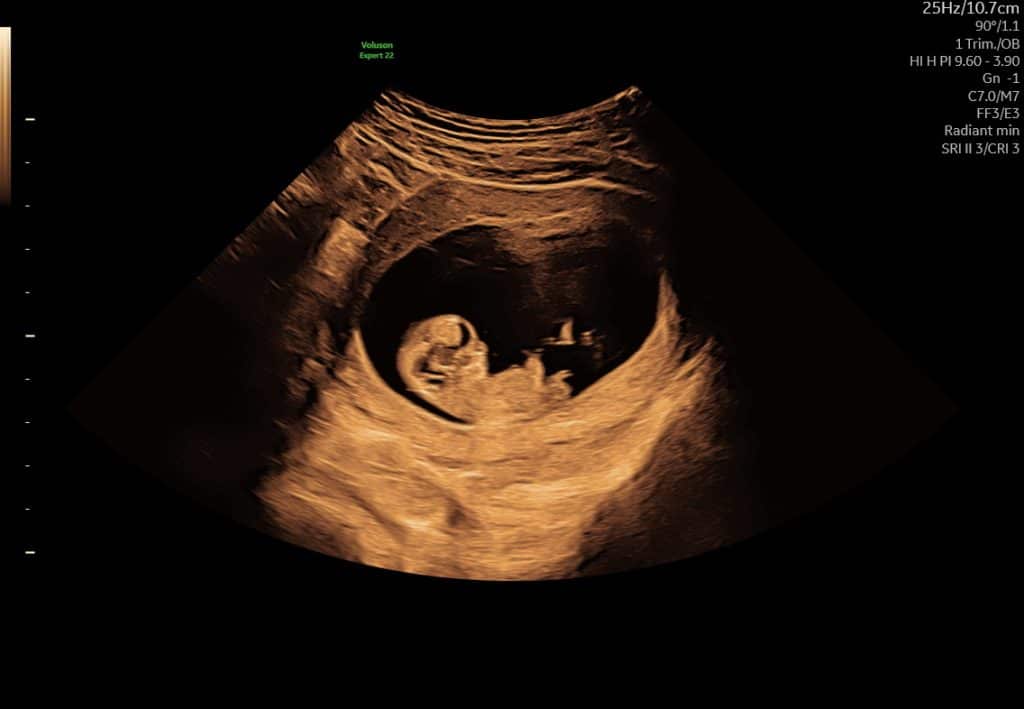

Ultralydsscanning uge 7 hjerteblink

Ultralydsscanning uge 8 lille foster i livmoderen

Eksempel på ultralyd i uge 7–8. Hjerteblink kan ofte ses, men synligheden varierer.

I denne periode kan bevægelse ofte ses tydeligere på video end på stillbilleder.

Kort ultralydssekvens fra uge 7, hvor hjerteaktivitet og tidlig bevægelse kan ses